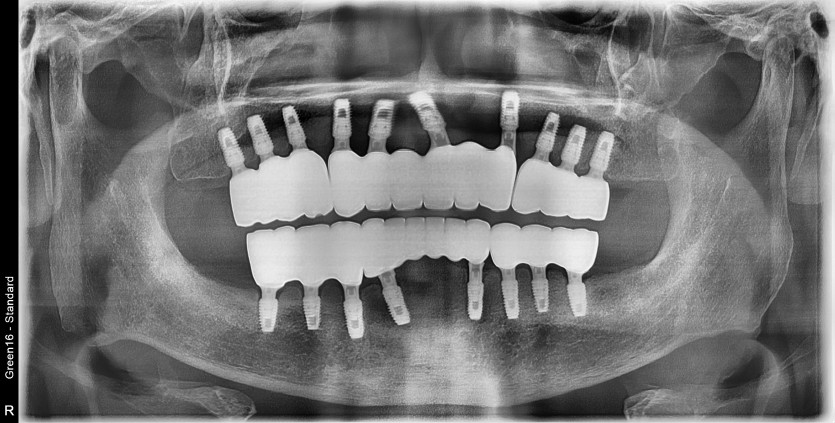

전체 임플란트 증례입니다.

18개의 임플란트로 완성하였습니다.